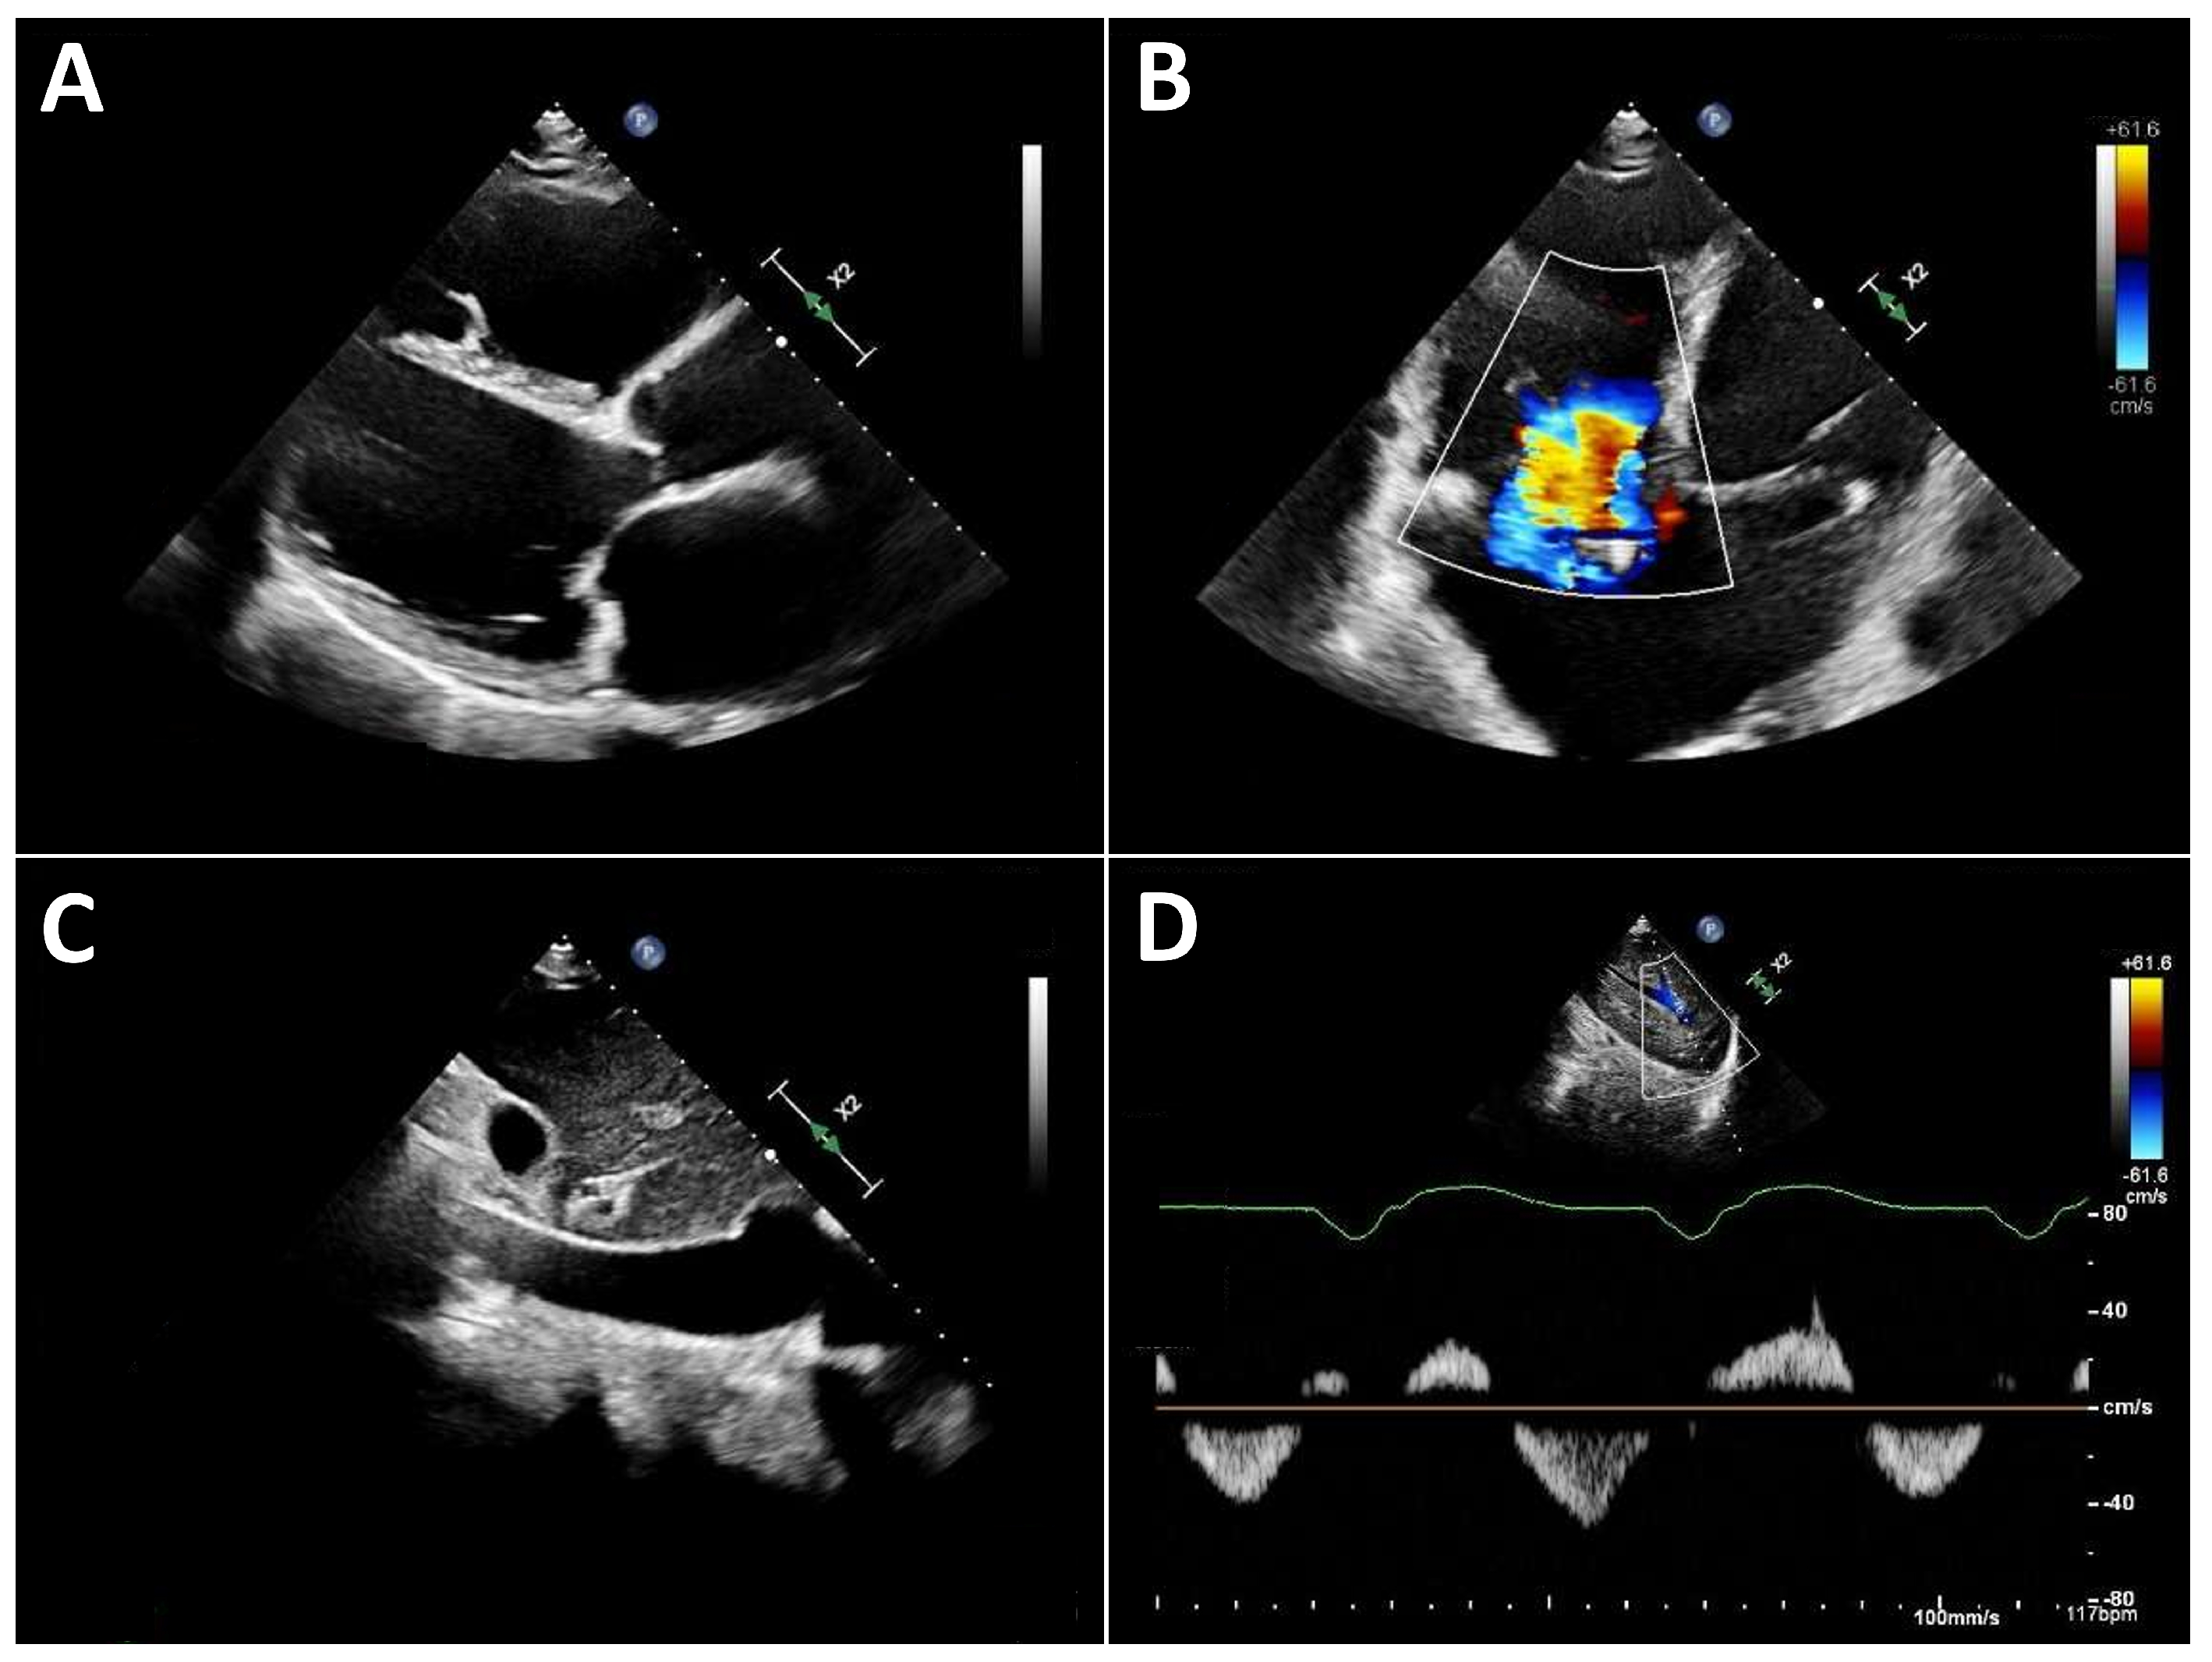

Typical echocardiographic signs of right ventricular failure include right ventricular dilatation, reflected by an increase in the proximal RV outflow tract (RVOT) diameter and RVD1 (Figure 3). This is frequently accompanied by dilatation of the tricuspid annulus with progressive tricuspid regurgitation. In severe cases, a leftward deviation in the interventricular septum may be observed. In advanced stages, the inferior vena cava is markedly dilated and exhibits significantly reduced respiratory variation. Quantification of tricuspid regurgitation can be performed using the standard guideline-recommended parameters, with a five-grade severity classification that has proven useful [31].

Figure 3.

Typical echocardiographic findings of severe right heart failure in a patient with LVAD support. (A): Parasternal long-axis view showing a markedly dilated and hypokinetic proximal RVOT. (B): Apical view demonstrating pronounced right ventricular dilatation and severe tricuspid regurgitation. (C): Markedly dilated inferior vena cava with severely reduced respiratory variation. (D): Systolic flow reversal in the hepatic veins.

Three-dimensional echocardiography of the right heart is often not feasible in many LVAD patients due to limited acoustic windows. Therefore, assessment of right ventricular (RV) function primarily relies on two-dimensional parameters. Longitudinal RV function is frequently reduced after cardiac surgery [32], a finding that is also observed in patients with LVAD support. Accordingly, tricuspid annular plane systolic excursion (TAPSE) typically decreases after LVAD implantation [7,33]. This reduction in longitudinal function is, however, partially compensated by an increase in radial RV contraction.

Consequently, right ventricular fractional area change (FAC) is recommended over TAPSE for the assessment of RV function in LVAD patients [34]. Importantly, RV function under LVAD support cannot be adequately characterized by a single parameter. Instead, it should always be interpreted in the context of preload (inferior vena cava filling), afterload (pulmonary artery pressure), septal position (reflecting adequate left ventricular filling), and the severity of tricuspid regurgitation.